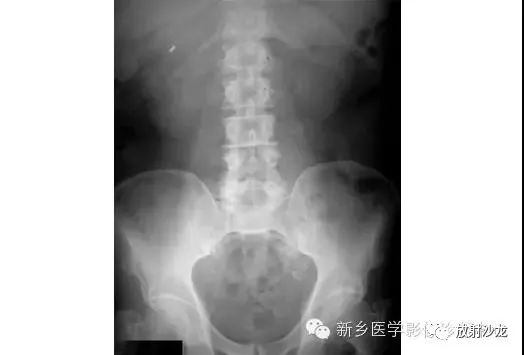

腹部平片解剖

腹部平片正常表现

腹部脏器有实质器官和空腔脏器之分,其正常腹平片表现不同。

● 腹平片上实质器官的正常表现:

实质器官:肝、胰、脾和肾等是中等密度,但借助于器官周围或邻近的脂肪组织和相邻充气肠胃的对比,于腹平片上,可显示器官的轮廓、大小、形状及位置。

正位片在部分病人可显示肝下缘,肝下缘与肝外缘相交形成肝角,一般呈锐角。

脾上极与左膈影融合,下极较圆钝。而肾沿腰大肌上部排列。

胰腺于平片上不易显示。子宫偶尔显影,位于膀胱上缘上方呈扁圆形软组织影。

● 空腔脏器在腹平片上的主要表现:

空腔器官:膀胱的脏壁为中、胆囊和肠胃道等密度,依腔内容物不同而x线表现不同。

胃、十二指肠球部及结肠内可含气体,于腹平片上可显示其内腔。小肠除婴幼儿可有积气外,一般充满食糜及消化液,与肠壁同属中等密度,因缺乏对比而不能显示。

如胃内有较多固态食物,结肠或直肠内有较多粪便,由于它们周围有气体衬托,故可显出软组织密度斑片或团块影。

结肠分布于腹部四周。膀胱和胆囊周围有较多脂肪,也可显示部分边缘。